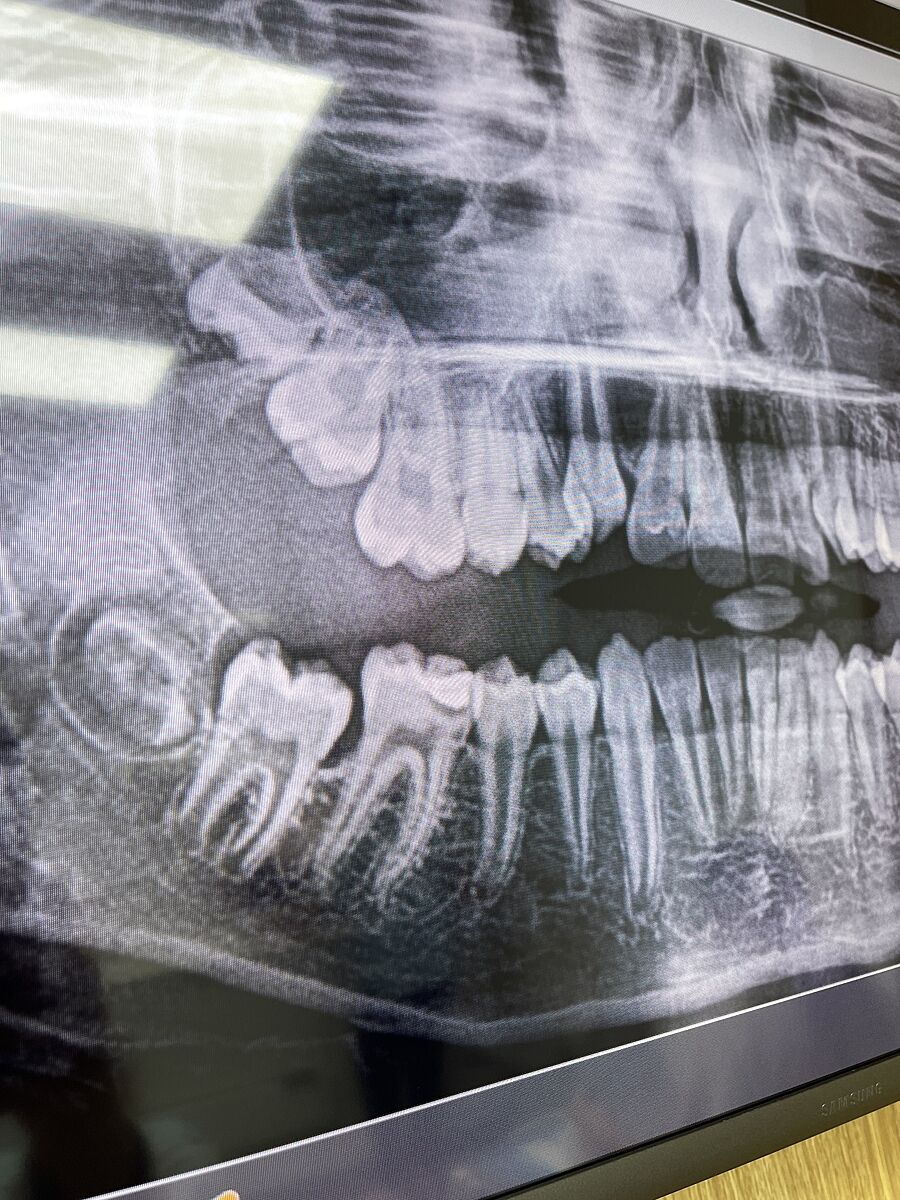

Після лікування карієсу болить зуб у дитини

Три дні нестерпного болю в зубі

Глибокий карієс під пломбою був ,робили знімок.

пролікували ,абе біль не пройшов